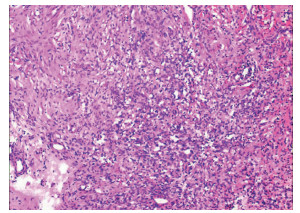

Lymphoepithelioma-like hepatocellular carcinoma: A case report

Xiaotong QIU, Zhengqi WU, Xuxiang XIA, Guoyue LYU

2022, 38(3): 634-635. DOI: 10.3969/j.issn.1001-5256.2022.03.027

Abstract(684) HTML (892) PDF (2924KB)(46)

Abstract: